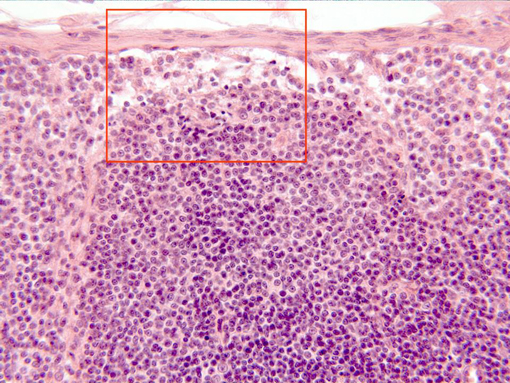

Aspect of the zone next to the ganglionary

capsule

observed with the objective of 40x. Under the capsule appear

the

subcapsular sine,

a looser arranged zone, and immediately underneath is

situated part of a

lymphatic follicle,

containing numerous lymphocytes showing blue-stained nuclei.

Details of the capsule and the sine can be examined in other

microphotography (area framed in red)